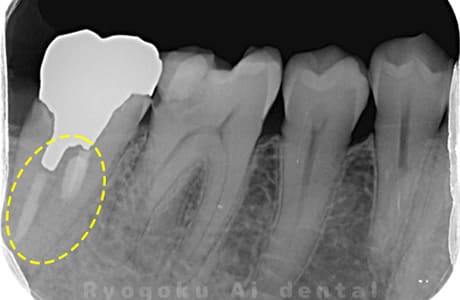

Case02

-

- 原因

- 慢性根尖性歯周炎

- 治療期間

- 3ヶ月

- 治療内容

- マイクロエンド

- 治療費用

- 121,000円

噛むと痛みが出る、とのことで来院した患者様です。他院での根管治療を終えてましたが、根尖病変を認めるため、マイクロエンドを行いました。